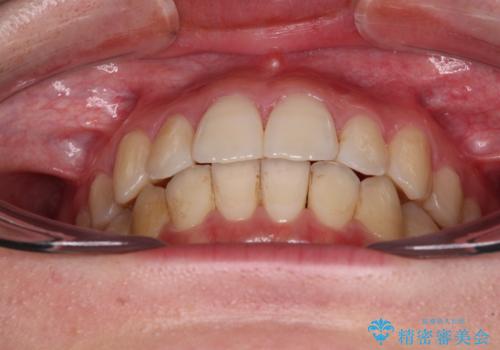

舌側転位している側切歯特有の、切縁の位置が不揃いであったり、根元が内側に引っ込んだ状態であったりという、インビザライン独特の仕上がりになることなく、きれいに整った歯列とすることができました。

- 前歯の突出感とクロスバイトが気になり、インビザラインによる矯正治療を希望して来院された患者様です。

【モニター】前歯の前突感とクロスバイトをインビザラインで改善